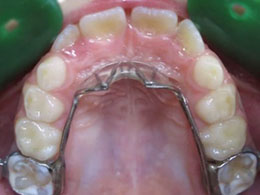

Il se pose sur la mâchoire supérieure et est constitué de deux bagues sur les molaires (anneaux métalliques qui entourent les dents), sur lesquelles une grille est soudée.

Grille vue d'en dessous